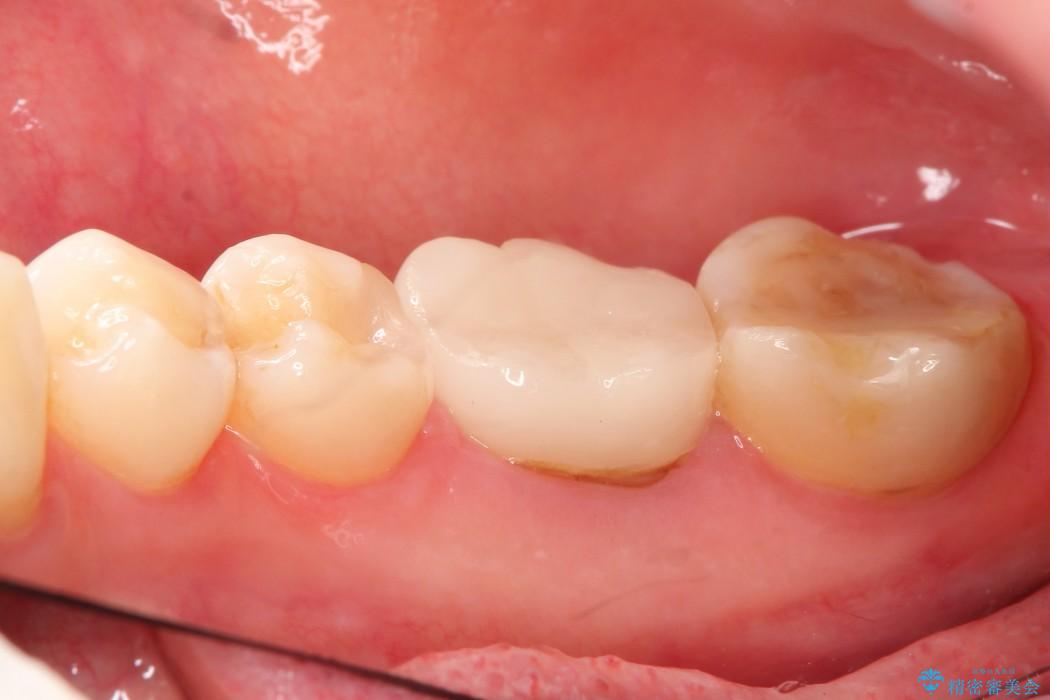

治療後について

抜歯を行った当日に骨の維持をする為、人工の骨を充填しました。インプラントを埋入する際には、ほとんどが自分の骨に置き換わっており、頬舌的なへこみを引き起こす事もなく、審美性・機能性ともに維持する事が出来ました。

また今回の治療では「バイコンインプラント」を使用する事により、インプラントの土台とセラミッククラウンを付ける際にセメントが全く残らないという利点を生かしたところ、見た目にも綺麗に仕上がり、患者様にも喜んでいただきました。